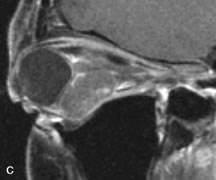

PATIENT PREPARATION Before MRI is performed, patients must be screened and prepared to avoid the potential hazards associated with the strong magnetic field. Patients who have ferrous aneurysm clips or cardiac pacemakers, who depend on life-support equipment, or who retain a possible metallic intraocular foreign body are not candidates for this imaging modality. MRI cannot be performed on obese patients who cannot fit into the bore of the magnet. Patients who are claustrophobic may not tolerate a prolonged period of study within the confines of the magnet, whereas others might do well if given a mild sedative. All worn metallic objects (e.g., necklaces, watches) should be taken off, credit cards set aside, and eye makeup removed before entering the room containing the magnet.5,20,34,35,36 NORMAL ORBITAL ANATOMY T1-weighted images provide the best anatomic details of the orbit because they display superior contrast resolution between normal structures (see Fig. 8). The vitreous has a long T1, resulting in an intermediate signal similar to brain, whereas the crystalline lens and sclera appear dark because of a longer T1 and short T2. The extraocular muscles, like all skeletal muscles, demonstrate a moderately long T1 and short T2 and highly contrast with the intense signal of the surrounding orbital fat (adipose tissue has an extremely short T1). The lacrimal glands appear as mottled areas of reduced intensity of the signal from the orbital fat in the lacrimal fossa. The optic nerves are seen with the same signal intensity as brain white matter and are hypointense relative to the orbital fat because their Tl is longer than the Tl of fat but shorter than the Tl of water. Cortical bone is not well delineated because it contains little free water, yielding minimal signal in MRI, and thus appears dark on all pulse sequences. This feature explains why MR images of the orbital apex and intracanalicular portion of the optic nerves are superior to comparable CT scans. Partial volume averaging of the bones in these regions obscures soft tissue details on CT images, whereas MRI reveals the signals only from the soft tissue structures with no cortical bone input. Bone marrow, on the other hand, is seen as a relatively intense signal because of its high fat content (see Fig. 8).37,38 T2-weighted pulse sequences are not ideal for imaging normal anatomy; however, they are particularly useful in revealing pathologic conditions (see Fig. 9). T2-weighted studies are most easily recognized by a bright vitreous signal. ORBITAL DISEASES Vascular Lesions Cavernous hemangiomas appear as well-circumscribed, smooth, usually intraconal masses that are isointense to muscle on T1-weighted images and hyperintense on T2-weighted images (Fig. 12). Patchy early enhancement is typically followed by diffuse, more homogeneous enhancement.39 The internal architecture of the mass, including septation and internal vasculature, may often be appreciated with high-quality orbital imaging.40 Lymphangiomas consist of ectatic vascular channels within a connective tissue stoma with varying degrees of lymphoid cellularity. On MRI, these tumors are typically poorly circumscribed, multicompartmental, and heterogeneous, often showing cystic dilations with fluid levels (Fig. 13). The signal characteristics within lymphangiomas vary considerably, reflecting cystic and solid components and the varying paramagnetic characteristics of blood at different stages of degradation.40–42 Acute hemorrhage appears hypointense on both T1- and T2-weighted formats. Methemoglobin present in subacute hemorrhage (3 to 14 days) leads to hyperintense signal on both T1- and T2-weighted images.41 A small percentage of lymphangiomas appear radiologically indistinct from orbital cavernous hemangiomas.43 Orbital varices are venous malformations that expand with increased systemic venous pressure, such as with Valsalva maneuvers. Because rapid acquisition of images during a Valsalva maneuver is important in imaging such a lesion, conventional or spiral CT is currently the modality of choice.44 MRI is an excellent modality for demonstrating enlargement of the cavernous sinus and dilation of the superior ophthalmic vein in patients with high-flow carotid-cavernous fistulas (Fig. 14).37MRA may be helpful in the evaluation of the venous outflow pattern. The rapidly flowing blood in these vascular structures carries the excited protons out of the section before they can be imaged, resulting in their dark appearance.5 In low-flow dural arteriovenous malformations, MRA may help define the arterial feeding vessels.45 Neural Lesions MRI is more effective than CT in delineating the intracranial optic nerves, chiasm, and optic tracts and, for this reason, is the preferred imaging modality in the evaluation of optic nerve disorders. The spatial relationships and image contrast of the orbital tissues with intraorbital optic nerve tumors is comparable between the two imaging modalities. The normal nerve is isointense to brain and appears enlarged and kinked owing to infiltration of an optic nerve glioma on T1-weighted images. Gliomas appear hyperintense on T2-weighted images and may be heterogeneous owing to cystic areas within the tumor. Contrast enhancement is variable.46 Intraorbital and intracranial optic nerve sheath meningiomas are usually isointense to cortical gray matter on Tl-weighted images and remain isointense on proton density studies (Fig. 15). Gd-DTPA is useful in delineating the intracranial extension of optic nerve meningiomas.7,47 The hyperostosis of bone and calcification associated with meningiomas are not demonstrated as well on MRI studies as on CT scans.20,37 Gd-DTPA–enhanced MRI also appears promising in the study of the permeability of the blood–brain barrier in selected optic neuropathies.22,48 MRI may reveal an enlarged optic nerve and some degree of contrast enhancement in cases of optic neuritis.49 Muscle Disorders Extraocular muscle enlargement in patients with thyroid-associated orbitopathy is demonstrated equally well with CT and MRI studies. However, the superior tissue contrast on MR images reveals better details of the relationships of the optic nerve to the thickened muscles at the orbital apex (Fig. 16).50 In addition, MRI may be able to differentiate between muscles that are enlarged as a result of edema and active inflammation and those enlarged because of fibrosis by their T2 relaxation times.21 Quantitative MRI was not found to be accurate in predicting the success of low-dose orbital irradiation.51 However, a muscular index relating the diameters of the rectus muscles to the bony orbital dimensions was useful in predicting optic nerve compression.52 MRI is also effective in imaging orbital tumors of mesenchymal origin, such as rhabdomyosarcoma, particularly in the assessment of extension into the anterior and middle cranial fossae (Fig. 17).37 The lack of any pathognomonic radiologic features necessitates rapid orbital biopsy when rhabdomyosarcoma is suspected. Osseous Lesions In general, CT is the imaging modality of choice when details of quantity and quality of bone are needed; however, abnormalities of bones can be detected indirectly by MRI. Cortical bone appears black (signal void) on MR images because of its low proton density and free-water content. The absence or discontinuity of the signal void of the orbital walls may represent bony destruction or fracture. Hyperostosis associated with prostate metastases or meningioma is visualized as areas of black smudging.50,53 Diseases in which the bone is replaced by pathologic tissues with a high free-water content, such as fibrous dysplasia, are well demonstrated on MRI. An intermediate signal intensity on T1-weighted images and hypointense signal on T2-weighted images is representative of fibrous dysplasia. Enhancement on post–Gd-DTPA MR scans is seen and is more evident in areas that are less mineralized.54 Cystic Lesions Dermoid cysts appear as rounded, well-defined lesions typically contiguous with an orbital bony suture. The high-intensity signal on T1-weighted images is attributed to the sebaceous-produced lipid contents (Fig. 18).31,50 Mucoceles may demonstrate a hypointense or hyperintense signal on MR images, depending on the concentration of proteinaceous or inflammatory fluid components. The integrity of the bony walls of the expanded sinus cavities cannot be assessed on MR as well as by CT.37,50,55,56 A high-signal intensity on Tl- and T2-weighted images is characteristic of orbital chronic hematic cysts because of the blood-breakdown products within the cysts.57 Trauma Although soft tissue relationships are usually better demonstrated on MRI, the evaluation of craniofacial bony trauma is preferable with CT. For example, prolapse of orbital fat through a fracture site and hemorrhage of adjacent tissues are demonstrated in an MR image, but the actual fractured bone is not imaged. Three-dimensional MRI of the orbit in subacute trauma has been described,58 although its precise role is not currently established. MRI has been suggested to be superior to CT in detecting intraorbital wooden foreign bodies.59,60 In a series of penetrating orbital injuries with organic foreign bodies, however, MRI was able to identify the foreign body in only four of seven cases.61 With an in vitro model for wood foreign body, McGuckin and colleagues concluded that CT was the imaging modality of choice.62 A careful history and, in selected cases, plain films to rule out a metallic foreign body are crucial before MRI is considered in patients with periocular trauma. MRI is particularly helpful in the detection and characterization of subperiosteal hematomas of the orbit (Fig. 19). They are most commonly seen in the subperiosteal space of the superior orbit as well-defined masses following a traumatic injury. The signal intensity varies depending on the acute, subacute, or chronic nature of the hematoma, based on the stage of blood degradation. Fresh hemorrhages are hypointense on T1-weighted images and hyperintense on T2 images. Hematomas that are 1 to 7 days old are hypointense on both T1- and T2-weighted images. T1-weighted images of hematomas more than a week old are hyperintense due to the oxidation of deoxyhemoglobin to methemoglobin, whereas the T2 images remain hypointense.63 Metastatic Tumors Breast carcinoma metastatic to the orbit has been demonstrated to be hypointense to the surrounding orbital fat on T1-weighted studies and hyperintense on T2-weighted images and has an affinity to the extraocular muscles (Fig. 20).50,64 The MRI characteristics of prostate carcinoma metastatic to the orbit have been described as involving the greater and lesser wing of the sphenoid, orbital roof, and optic canal. Diffuse bone hypertrophy with isointense or slightly hyperintense tissue on T1-weighted images represents the osteoblastic carcinomatous bone infiltration. Contrast enhancement is variable on T1-weighted and fat-suppressed images.65 Most other metastatic tumors also have a lower intensity signal on T1-weighted images and appear to displace or infiltrate normal orbital structures; however, their signal characteristics are variable on T2-weighted MR images.66 Many metastatic tumors demonstrate bright contrast enhancement with Gd-DTPA. Infectious Disorders MRI findings of preseptal and orbital cellulitis typically include increased signal intensities on T2-weighted images of the eyelids and orbital fat, respectively, due to the increased water content of the tissues. Since most cases of bacterial orbital cellulitis are associated with paranasal sinusitis, hyperintense signals of the affected sinuses may also be found on T2-weighted images as well as enhancement of polyps and granulation tissue on postgadolinium T1-weighted MR images. Subperiosteal abscess formation may occur due to contiguous spread of infection from the paranasal sinuses and appear on MRI as an area of intermediate signal on T1-weighted and proton-weighted MR images. The abscess may appear slightly hyperintense compared with muscle on T2-weighted scans with the necrotic contents having the greatest intensity.67 MRI and MRV are more sensitive than CT in revealing cavernous sinus thrombosis. Engorgement of the cavernous sinus, extraocular muscles, and ophthalmic veins is seen with hyperintensity of the thrombosed sinuses evident on all pulse sequences. The enlarged, thrombosed superior ophthalmic vein appears less hypointense than the normal contralateral ophthalmic vein, and hyperintensity within the lumen of the vessel may be seen on T1- and T2-weighted MR images.68 Inflammatory and Lymphoproliferative Lesions Inflammatory conditions of the orbit, both idiopathic (inflammatory pseudotumor) and those of known causes, have been found to be hypointense to fat and isointense to muscle on Tl-weighted studies and isointense or slightly hyperintense to fat on T2-weighted images (Fig. 21).50,64,69 The more fibrous or sclerosing varieties have less signal intensity on T2-weighted images. Marked enhancement is seen in pseudotumor infiltrates after gadolinium administration.70 The same signal characteristics are demonstrated in patients with Tolosa-Hunt syndrome, with mass lesions seen in the cavernous sinuses and orbital apices.71 Lymphomas have MRI characteristics similar to those of inflammatory lesions in that they are hypointense to fat and isointense to muscle on T1-weighted images (Fig. 22). They may appear hyperintense to fat on T2-weighted images, perhaps owing to less fibrosis than that seen in orbital inflammatory pseudotumor, although this is not a consistent finding.31,50,66 Lymphoid tumors typically enhance moderately after contrast injection. Unfortunately, studies have shown that tumor density and homogeneity are similar between inflammatory and malignant orbital infiltrates, and MRI cannot differentiate these lesions.72,73 Lacrimal Gland Tumors Lacrimal gland lesions present special problems in diagnosis and management. Pleomorphic adenoma (benign mixed tumor) should not be biopsied, but rather excised in toto. On the other hand, for lymphoma and inflammatory infiltrates, incisional biopsy is more appropriate than complete excision of the lacrimal gland. Thus, preoperative clinical and radiologic evaluation are especially crucial in planning appropriate surgical management. Pleomorphic adenomas demonstrate long T1 and T2 signal characteristics. They may show heterogeneity on T2-weighted images74 and moderate to marked enhancement with contrast.75 Signal characteristics of adenoid cystic carcinoma include hypointensity to fat on T1-weighted images, hyperintensity to fat with increased T2 weighting, and isointensity to fat on proton density-weighted studies (Fig. 23).31,75 Secondary bony alterations of the lacrimal fossa associated with lacrimal gland tumors, such as remodeling (benign mixed tumor) or destruction (adenoid cystic carcinoma), are seen indirectly on MR images; however, bone windows on CT scans provide better delineation of these changes. In contrast to the round or globular appearance of benign or malignant epithelial tumors of the lacrimal gland, lymphoproliferative tumors usually appear to be molding or draping onto the globe and the surrounding bony orbit. LACRIMAL DRAINAGE SYSTEM DISORDERS MRI with surface coils provides excellent spatial resolution and tissue-specific signal intensities of the lacrimal drainage system. These parameters have been found useful to more accurately demonstrate the extent of lesions in the lacrimal sac and differentiate long-standing mucoceles from solid tumors than CT.76 Physiologic studies in patients with tearing disorders now include MR dacryocystography, in which Gd-DTPA is either placed topically in the conjunctival fornix or injected by cannulation into the lacrimal sac. They provide a detailed morphologic and functional analysis of the lacrimal excretory system; however, they are no more sensitive than digital-subtraction dacryocystography or CT dacryocystography.77–79 INTRAOCULAR TUMORS On MRI, uveal melanomas have a typical appearance that helps to differentiate them from other primary and secondary intraocular tumors as well as choroidal detachments. Pigmented melanomas are hyperintense on Tl-weighted images, hypointense on T2-weighted studies, and hyperintense on proton density–weighted examinations (Fig. 24).30,31,50,80–82 These signal characteristics have been attributed to the paramagnetic properties of melanin because of stable free radicals that shorten the T1 and T2 relaxation times. Moderate enhancement is seen on postgadolinium T2-weighted images. Gadolinium-enhanced T1-weighted images are particularly sensitive in detecting choroidal melanomas.83 MRI may be less sensitive in detecting extrascleral extension of tumor than echography performed by an experienced ultrasonographer.84 Tumors metastatic to the choroid are hyperintense on T1- and T2-weighted images.24 The signal characteristics, however, may be similar to those seen with choroidal melanoma. Choroidal hemangiomas, on the other hand, have an intermediate signal on T1-weighted sequences and become hyperintense on T2-weighted images50 as well as proton density–weighted images.81 Retinoblastomas display moderate signal intensity on T1-weighted studies and a low signal on T2-weighted images.31,80,85 Calcification can be easily detected by CT and ocular ultrasonography but is not imaged by MRI.25,50 The presence of optic nerve involvement is best evaluated by MRI. ACQUIRED ANOPHTHALMIA When an eye is removed owing to tumor or trauma, an implant is typically placed in the intraconal space. MRI may be useful in defining the size, shape, and position of such orbital implants.86 Porous hydroxyapatite or polyethylene implants are preferred by many surgeons performing enucleation or evisceration. A porous implant offers the possibility of supporting a motility coupling peg to increase the movement of the overlying prosthesis. MRI with contrast is used by some surgeons to evaluate the degree of fibrovascular ingrowth in hydroxyapatite87 and porous polyethylene88 implants prior to motility peg placement. |